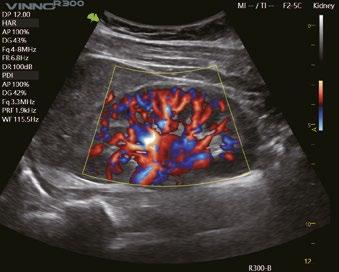

Erkennung der Fließgeschwindigkeit des Blutes. Es ermöglicht eine feinere Diagnose, bei besonders schwierigen Untersuchungen des Blutflusses.

Eine innovative Technologie, die die Visualisierung des Blutflusses verbessert, indem sie eine 3D-Darstellung der Farb-/Power-Doppler-Bildgebung anzeigt.